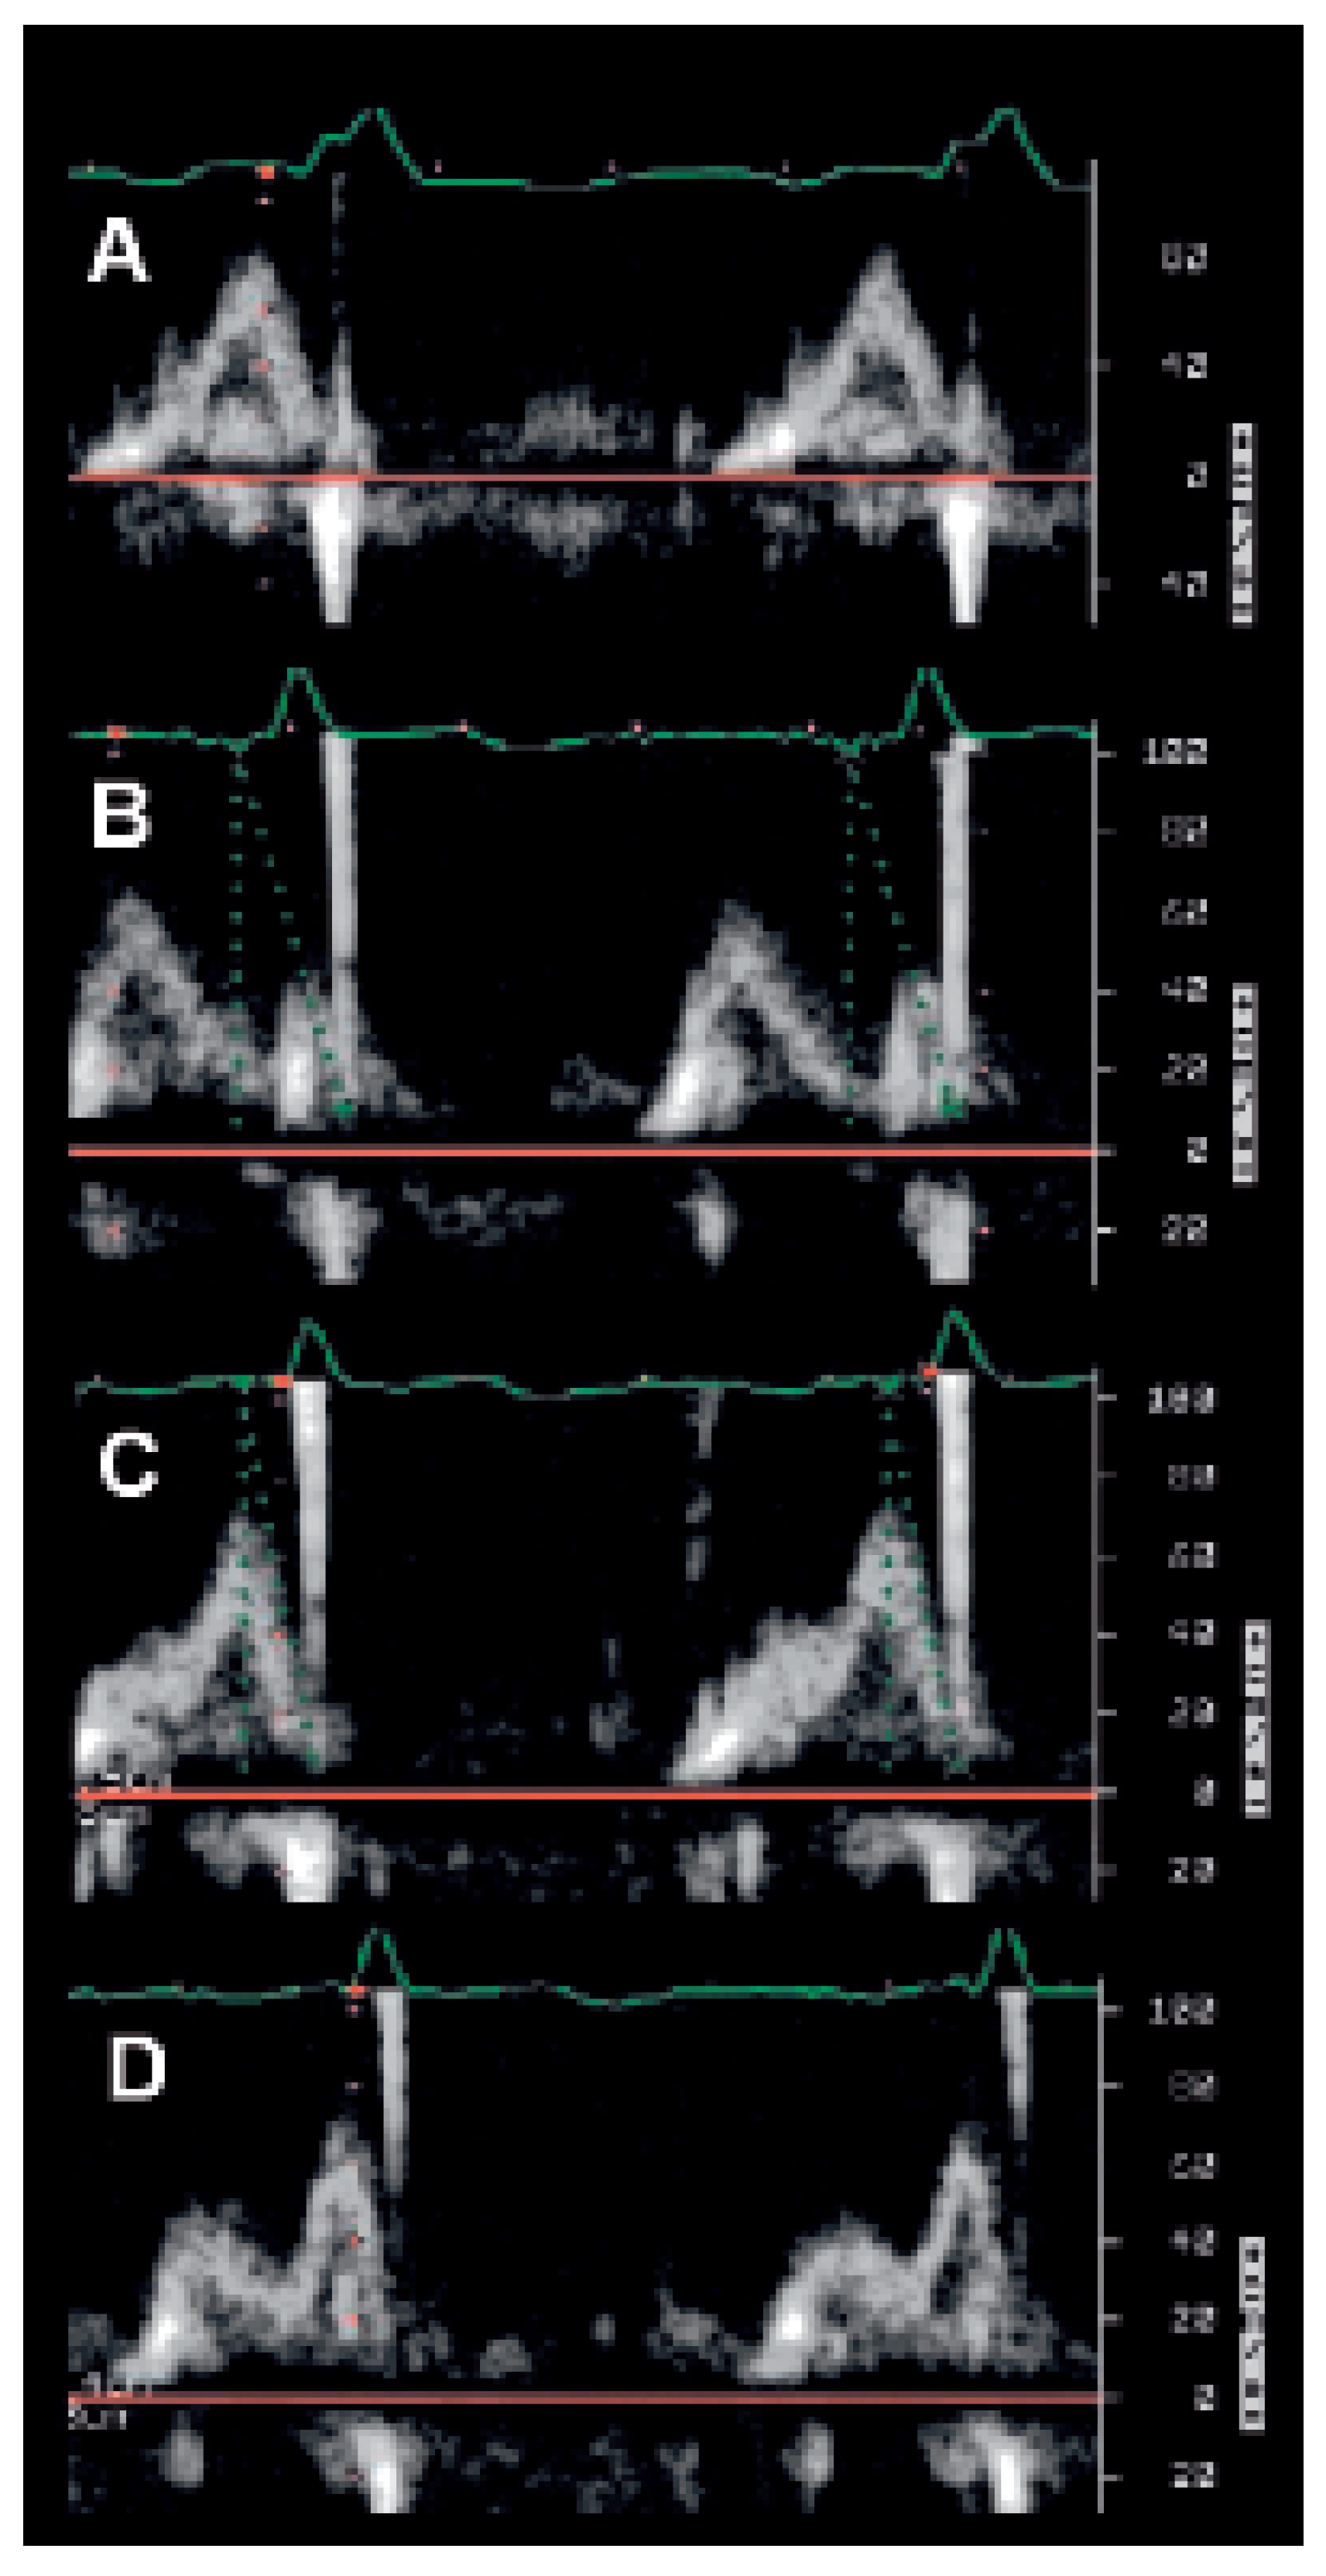

Conventional Doppler echography

VV interval optimisation